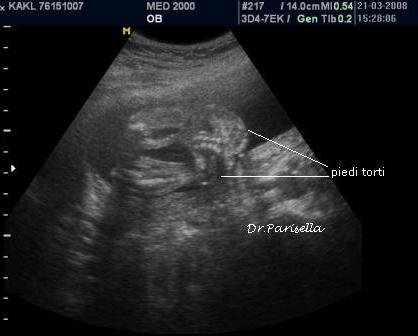

La Diagnosi Prenatale Ecografica si basa su:

2) contratture multiple.